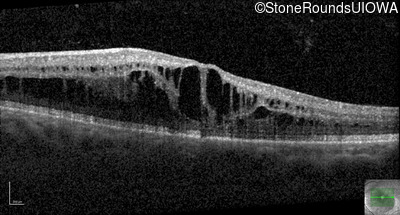

Optical Coherence Tomography - Right - 20/32 -1

Exemplar / OCT Stack

OCT Stack